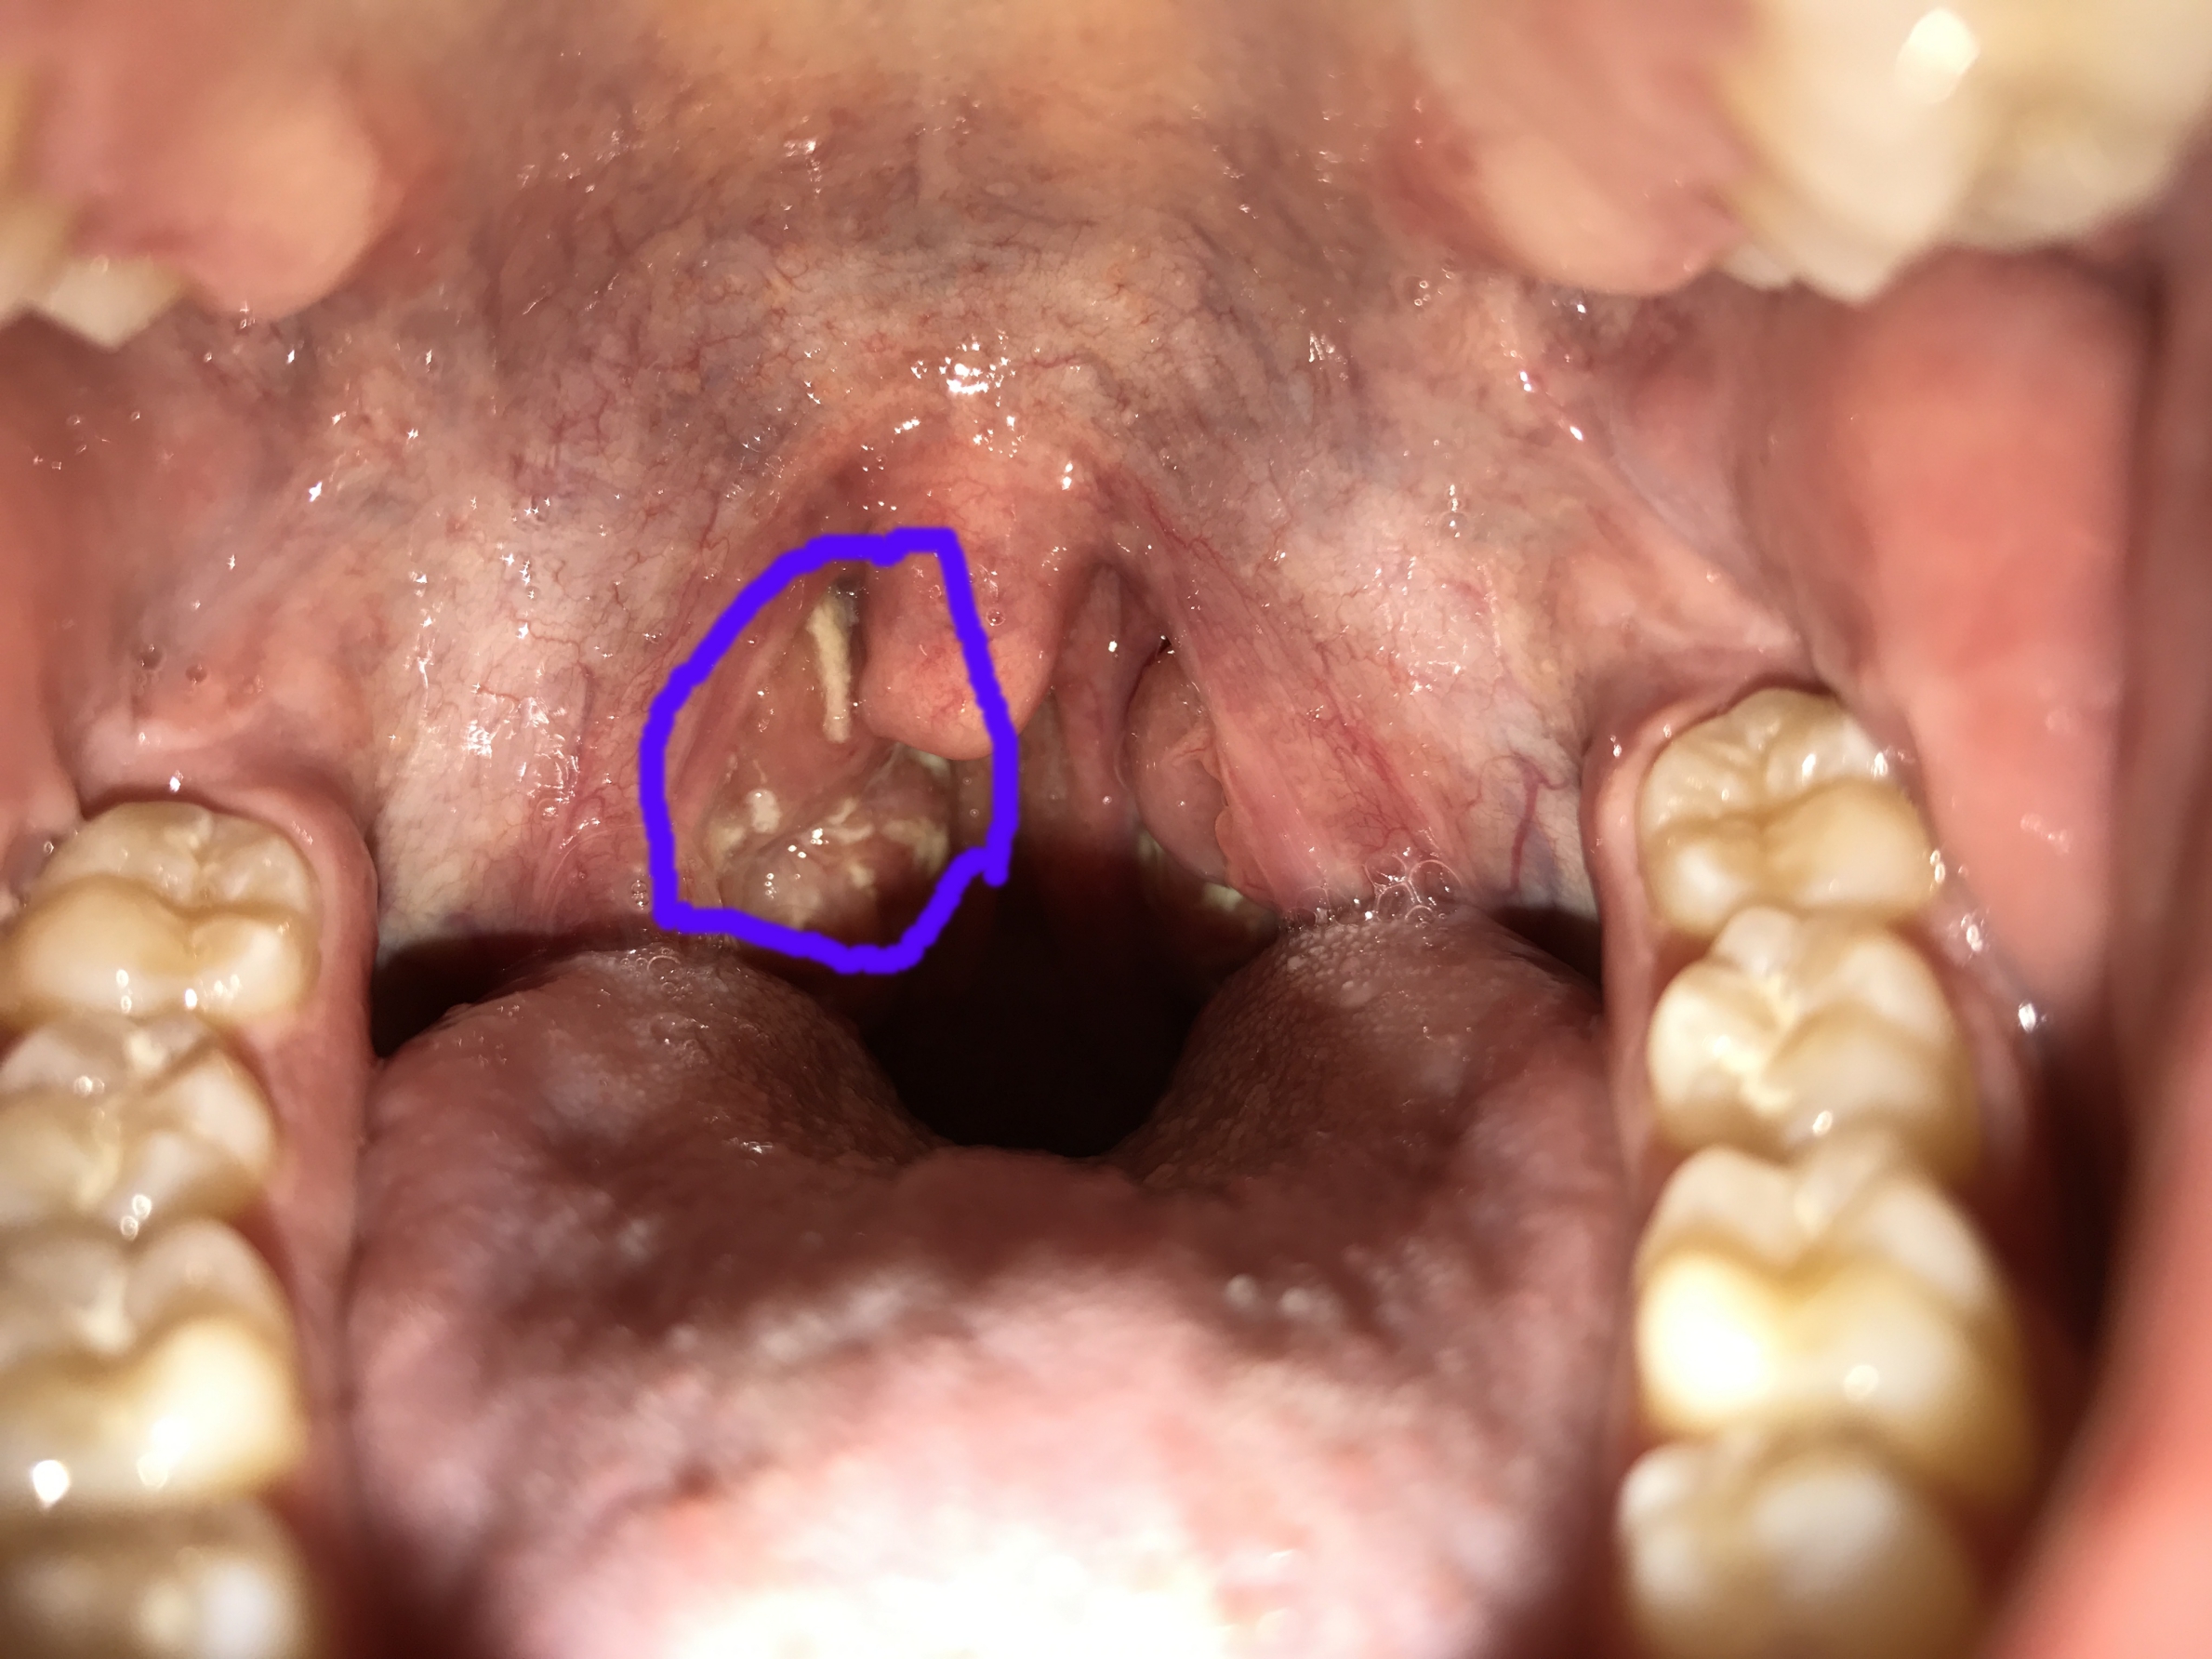

Eitrige Mandelentzündung oder doch mehr (siehe Bild)? (Bilder, krank